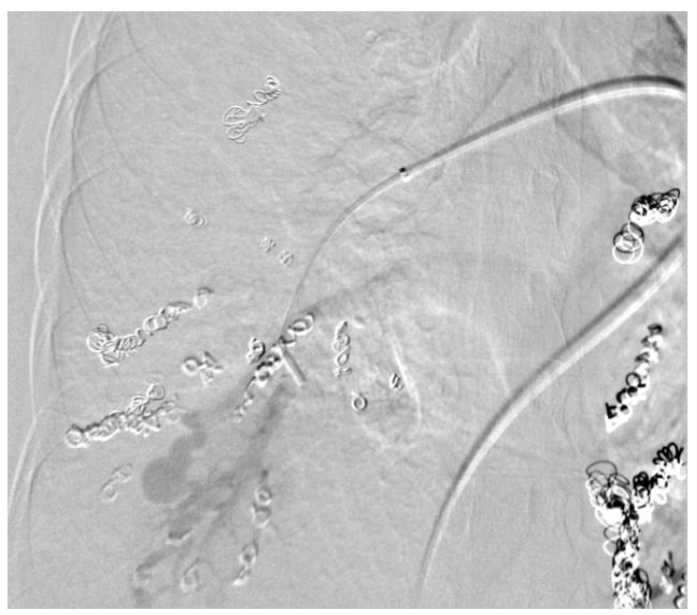

The recommended imaging studies were significant for numerous bilateral PAVM and she underwent placement of 10 total vascular coils antenatally. Unfortunately, the largest PAVM measured 32mm and was located within the left lingula, where a feeding vessel could not be identified. The next largest PAVM measured 17 mm (located in the right lower lobe) and 23 mm (located in the right upper lobe), both of which were successfully treated.

On postpartum day 1, the patient experienced an episode of acute onset hemoptysis, oxygen desaturation, tachycardia, and tachypnea. Prompt laboratory and imaging studies were obtained and pulmonology, anesthesia, and high-risk obstetrics were consulted. The patient immediately returned to the ICU where she was intubated due to persistent hypoxia. Repeat chest imaging was consistent with pulmonary hemorrhage. This was managed with urgent PAVM embolization, at which time a total of 4 vascular coils were placed in a right lower lobe PAVM that measured 17 mm. Notably, this was not one of the larger PAVMs targeted during antenatal embolization. The patient was subsequently extubated on postpartum day 3 and returned to the postpartum floor on postpartum day 4. The remainder of her hospital course was unremarkable and she was discharged home on postpartum day 5 in stable condition with appropriate follow up.